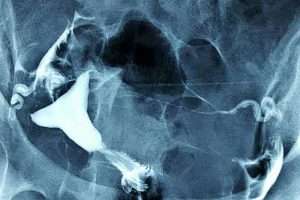

Myom

Rahim sağındaki iri myom kitlesi rahim boşluğu alt kısmının uzamasına ve sola doğru itilmesine sebep olmuş.